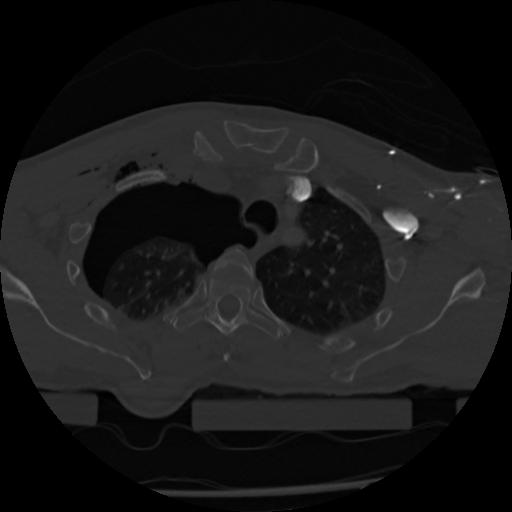

22 ANGIO,CE,Vol,0.5,ANGIO,,